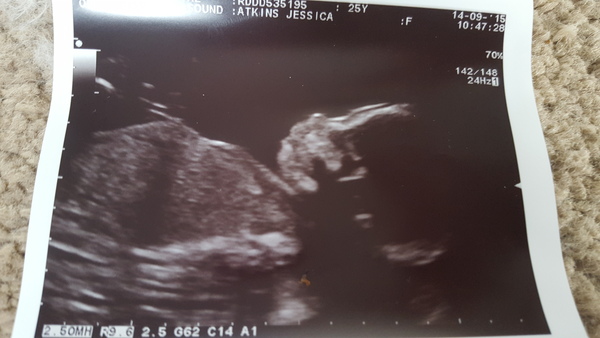

For those not on FB scan was all good, confirmed baby is a girly! Baby healthy but a trouble maker. She wouldn't sit still so I had to go for a walk and eat a chocolate bar.